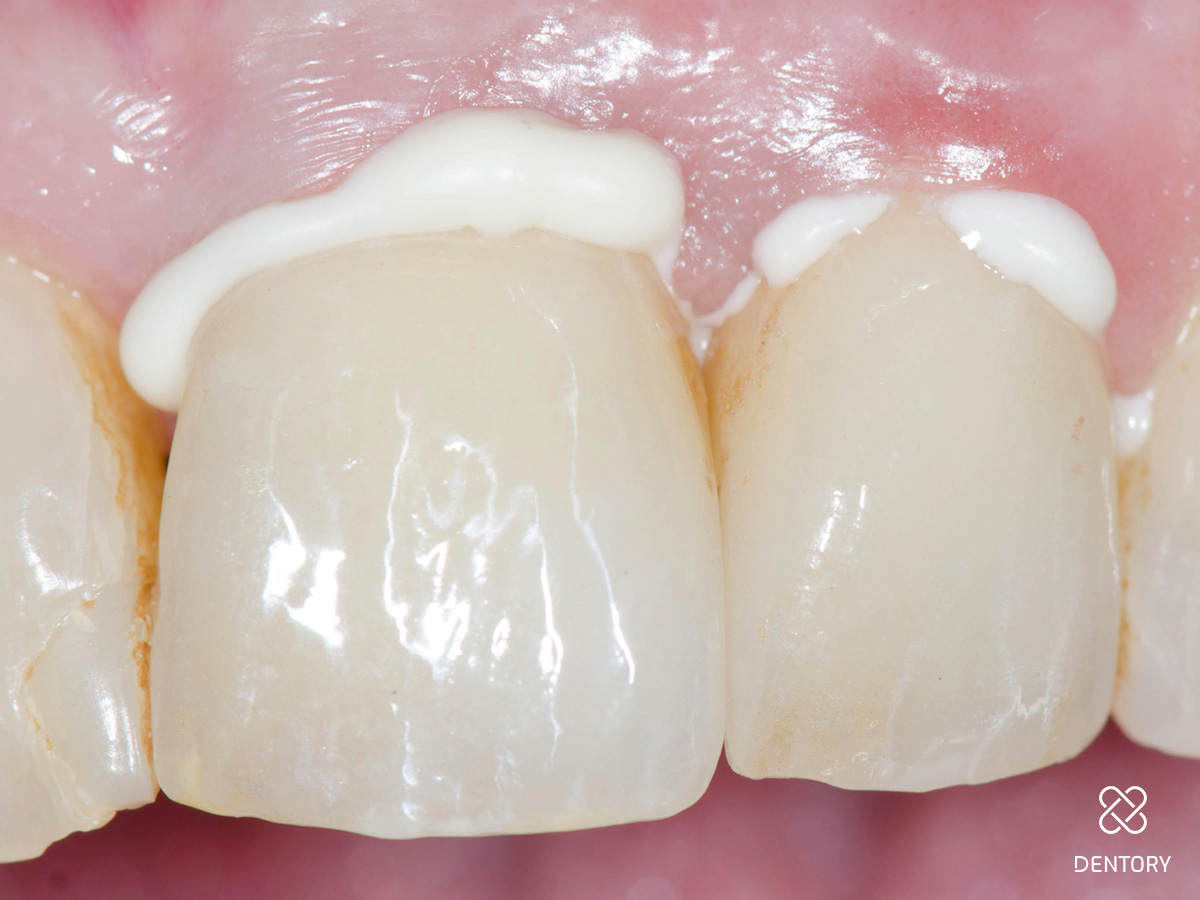

Abbildung 2

wurden ein ästhetisches Defizit wegen insuffizienter Kronenränder sowie Sekundärkaries an den Zähnen 21 und 22 diagnostiziert.